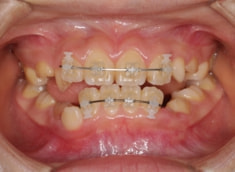

治療前